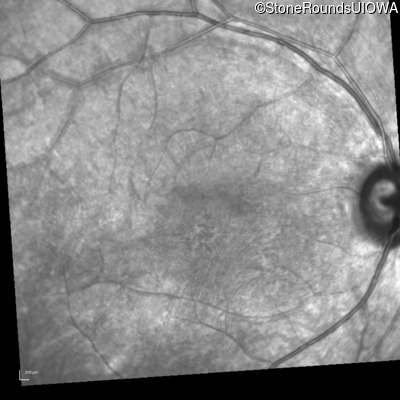

Infrared Fundus Photograph - Left - 20/100 -2 sc

Exemplar